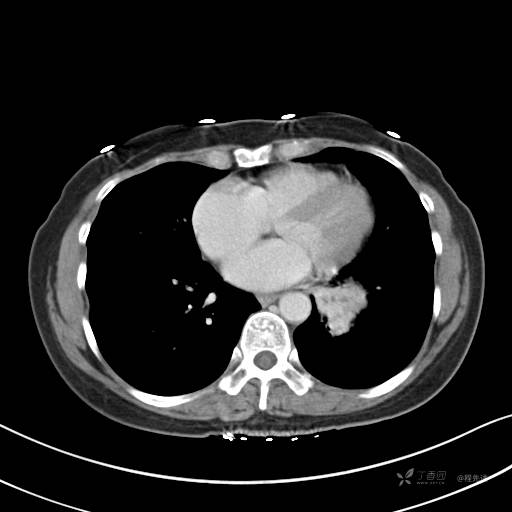

冠状位重建

CT值:平扫:31HU,动脉期:74HU,静脉期:84HU